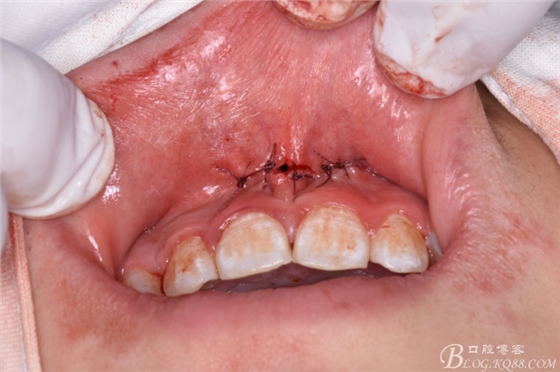

圖19.縫合創(chuàng)口

圖20. 在12、13根尖所對應(yīng)的前廳溝處做第二個弧形切口